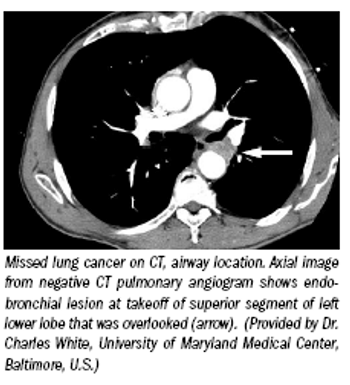

Radiologists may have to make only minor changes to their practices to adjust to the new international standards for lung cancer staging, but a lecture covering their implications was still controversial enough to send sparks flying Aug. 4 at the World Conference on Lung Cancer in San Francisco.